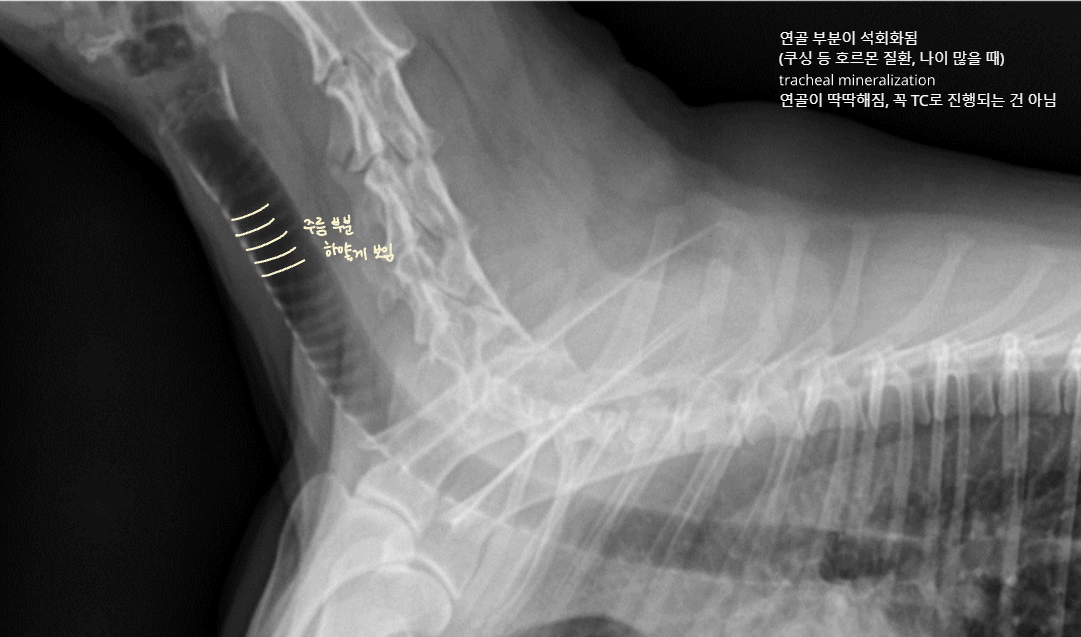

| Tracheal mineralization (์ฐ๊ณจ ๊ฒฝํ) |

![]() - ๋ ธํ, ํธ๋ฅด๋ชฌ ์งํ(Cushing ๋ฑ) |